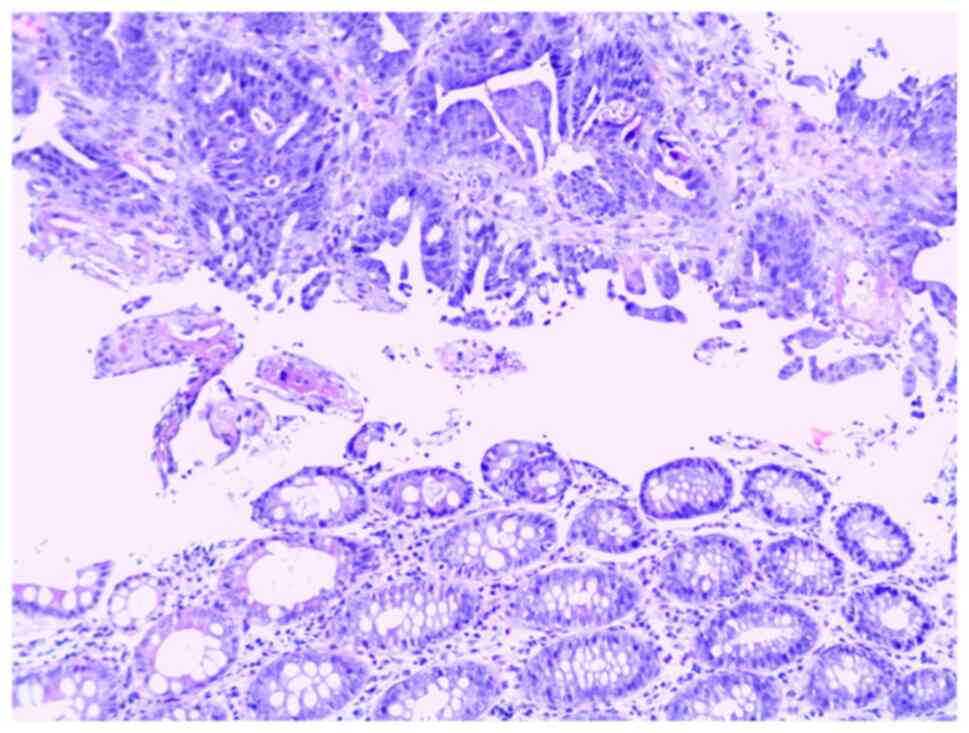

Familial Lynch syndrome with early age of onset and confirmed splice site mutation in MSH2: A case report

Lynch syndrome (LS) is an autosomal dominant cancer syndrome. It can be caused by mutations of several genes, including MLH1, MSH2, MSH6, PMS2, MLH3 and MSH3, which are responsible for DNA mismatch repair, and LS affects 3‑5% of patients with colorectal cancer (CRC). LS is associated with a high risk of cancer in several different locations, although the most commonly affected regions are the colon (20‑70% risk), endometrium (15‑70% risk), stomach (6‑13% risk) and ovaries (4‑12% risk). In the present report, the familial case of LS with a detected pathogenic variant in the MSH2 gene is described. The proband was a male who was diagnosed with CRC at the age of 25 years. Genealogy analysis revealed a total of seven affected relatives (including the proband), one of whom (I degree relative, mother) had synchronous cancers (endometrial and ovarian) and five others (of II and III degree relation) had ovarian cancer. Genetic analysis using next generation sequencing detected a heterozygous germline mutation in the MSH2 gene (c.1386 + 1G >A) in the proband and his mother, confirming the diagnosis of LS. The results of the recommended genetic test in an asymptomatic relative of the proband (II degree relative, uncle), found the same familial mutation. Subsequent prophylactic colonoscopy of this relative revealed early stage CRC. The presented case confirms the need for specific genetic analysis, alongside genetic counseling, in hereditary cancer syndromes. Active genetic prophylaxis in patients with LS allows early detection of primary cancers in other locations, and pre‑symptomatic genetic analysis of relatives is an option for early diagnosis.

Figure 1

Figure 2

Figure 3